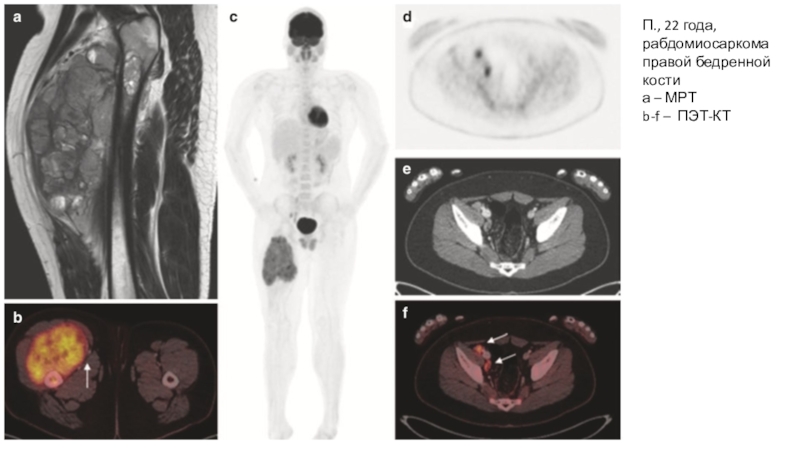

Слайд 15П., 22 года, рабдомиосаркома правой бедренной кости

а – МРТ

b-f –

ПЭТ-КТ

П., 22 года, рабдомиосаркома правой бедренной костиа – МРТb-f – ПЭТ-КТ